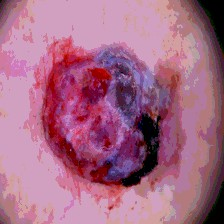

Timely identification and treatment of rapidly progressing skin cancers can significantly contribute to the preservation of patients' health and well-being. Dermoscopy, a dependable and accessible tool, plays a pivotal role in the initial stages of skin cancer detection. Consequently, the effective processing of digital dermoscopy images holds significant importance in elevating the accuracy of skin cancer diagnoses. Multilevel thresholding is a key tool in medical imaging that extracts objects within the image to facilitate its analysis. In this paper, an enhanced version of the Mud Ring Algorithm hybridized with the Whale Optimization Algorithm, named WMRA, is proposed. The proposed approach utilizes bubble-net attack and mud ring strategy to overcome stagnation in local optima and obtain optimal thresholds. The experimental results show that WMRA is powerful against a cluster of recent methods in terms of fitness, Peak Signal to Noise Ratio (PSNR), and Mean Square Error (MSE).